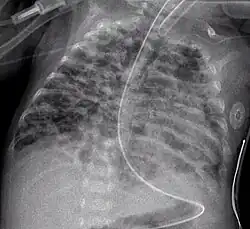

Chest film showing increased opacity in both lungs, indicative of pneumonia -